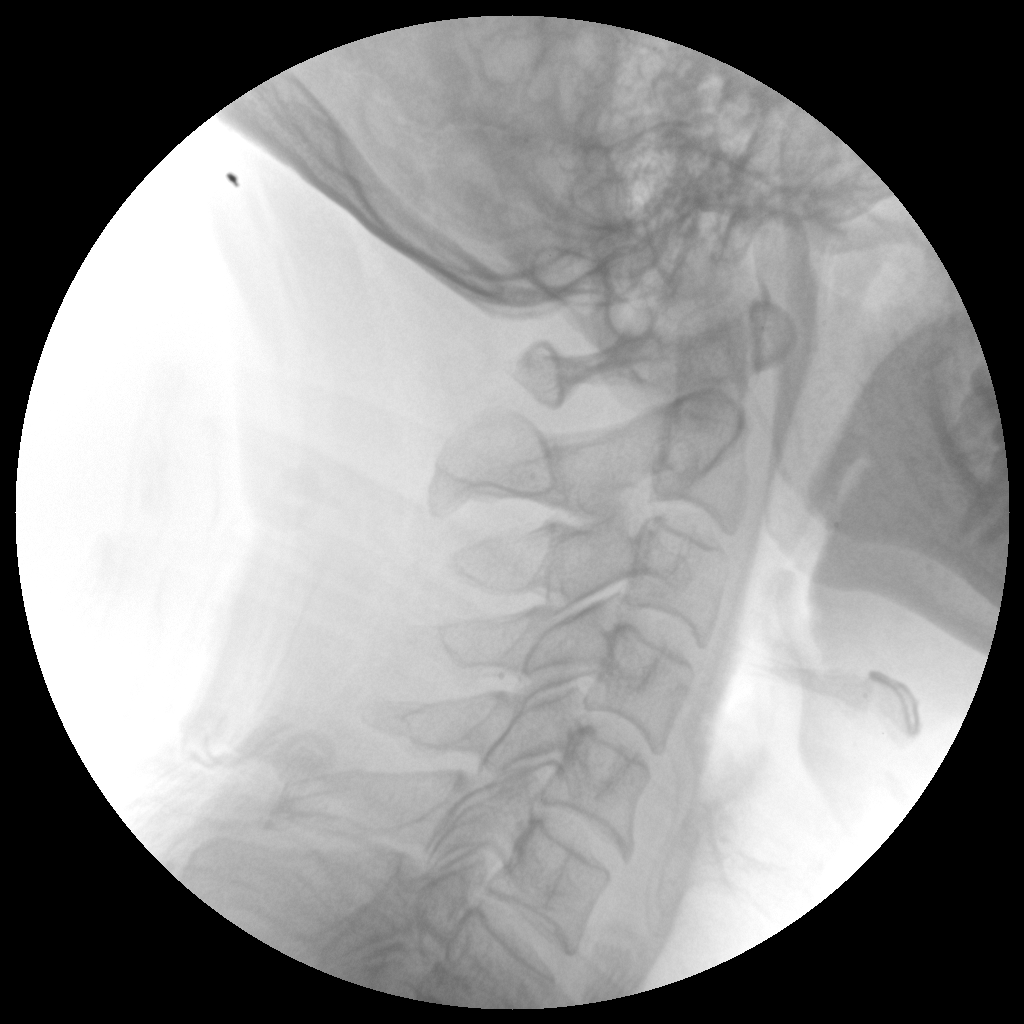

Clinical picture

臨床圖片